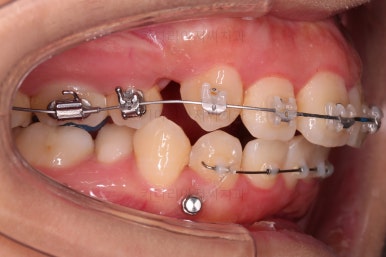

장치를 부착합니다.

이번 환자분이 선택한 장치는 엠파워 클리어라고 하는 자가결찰 세라믹 장치인데요.

철사를 묶는(결찰) cap이 장치에(자가) 달려있는 장치 중에 세라믹 성분으로 되어 심미성이 우수한 브라켓입니다.

대표적으로는 클리피씨 장치 등이 있습니다.

우선은 적응을 위해서 윗니만 장치를 부착하고요.

아랫니는 과개교합 개선을 위해 앞니 먼저 시작합니다.

아래 앞니는 깊숙하게 솟구쳐 오른 치아를 밑으로 끌어내리기 위해 미니스크류를 식립하게 됩니다.